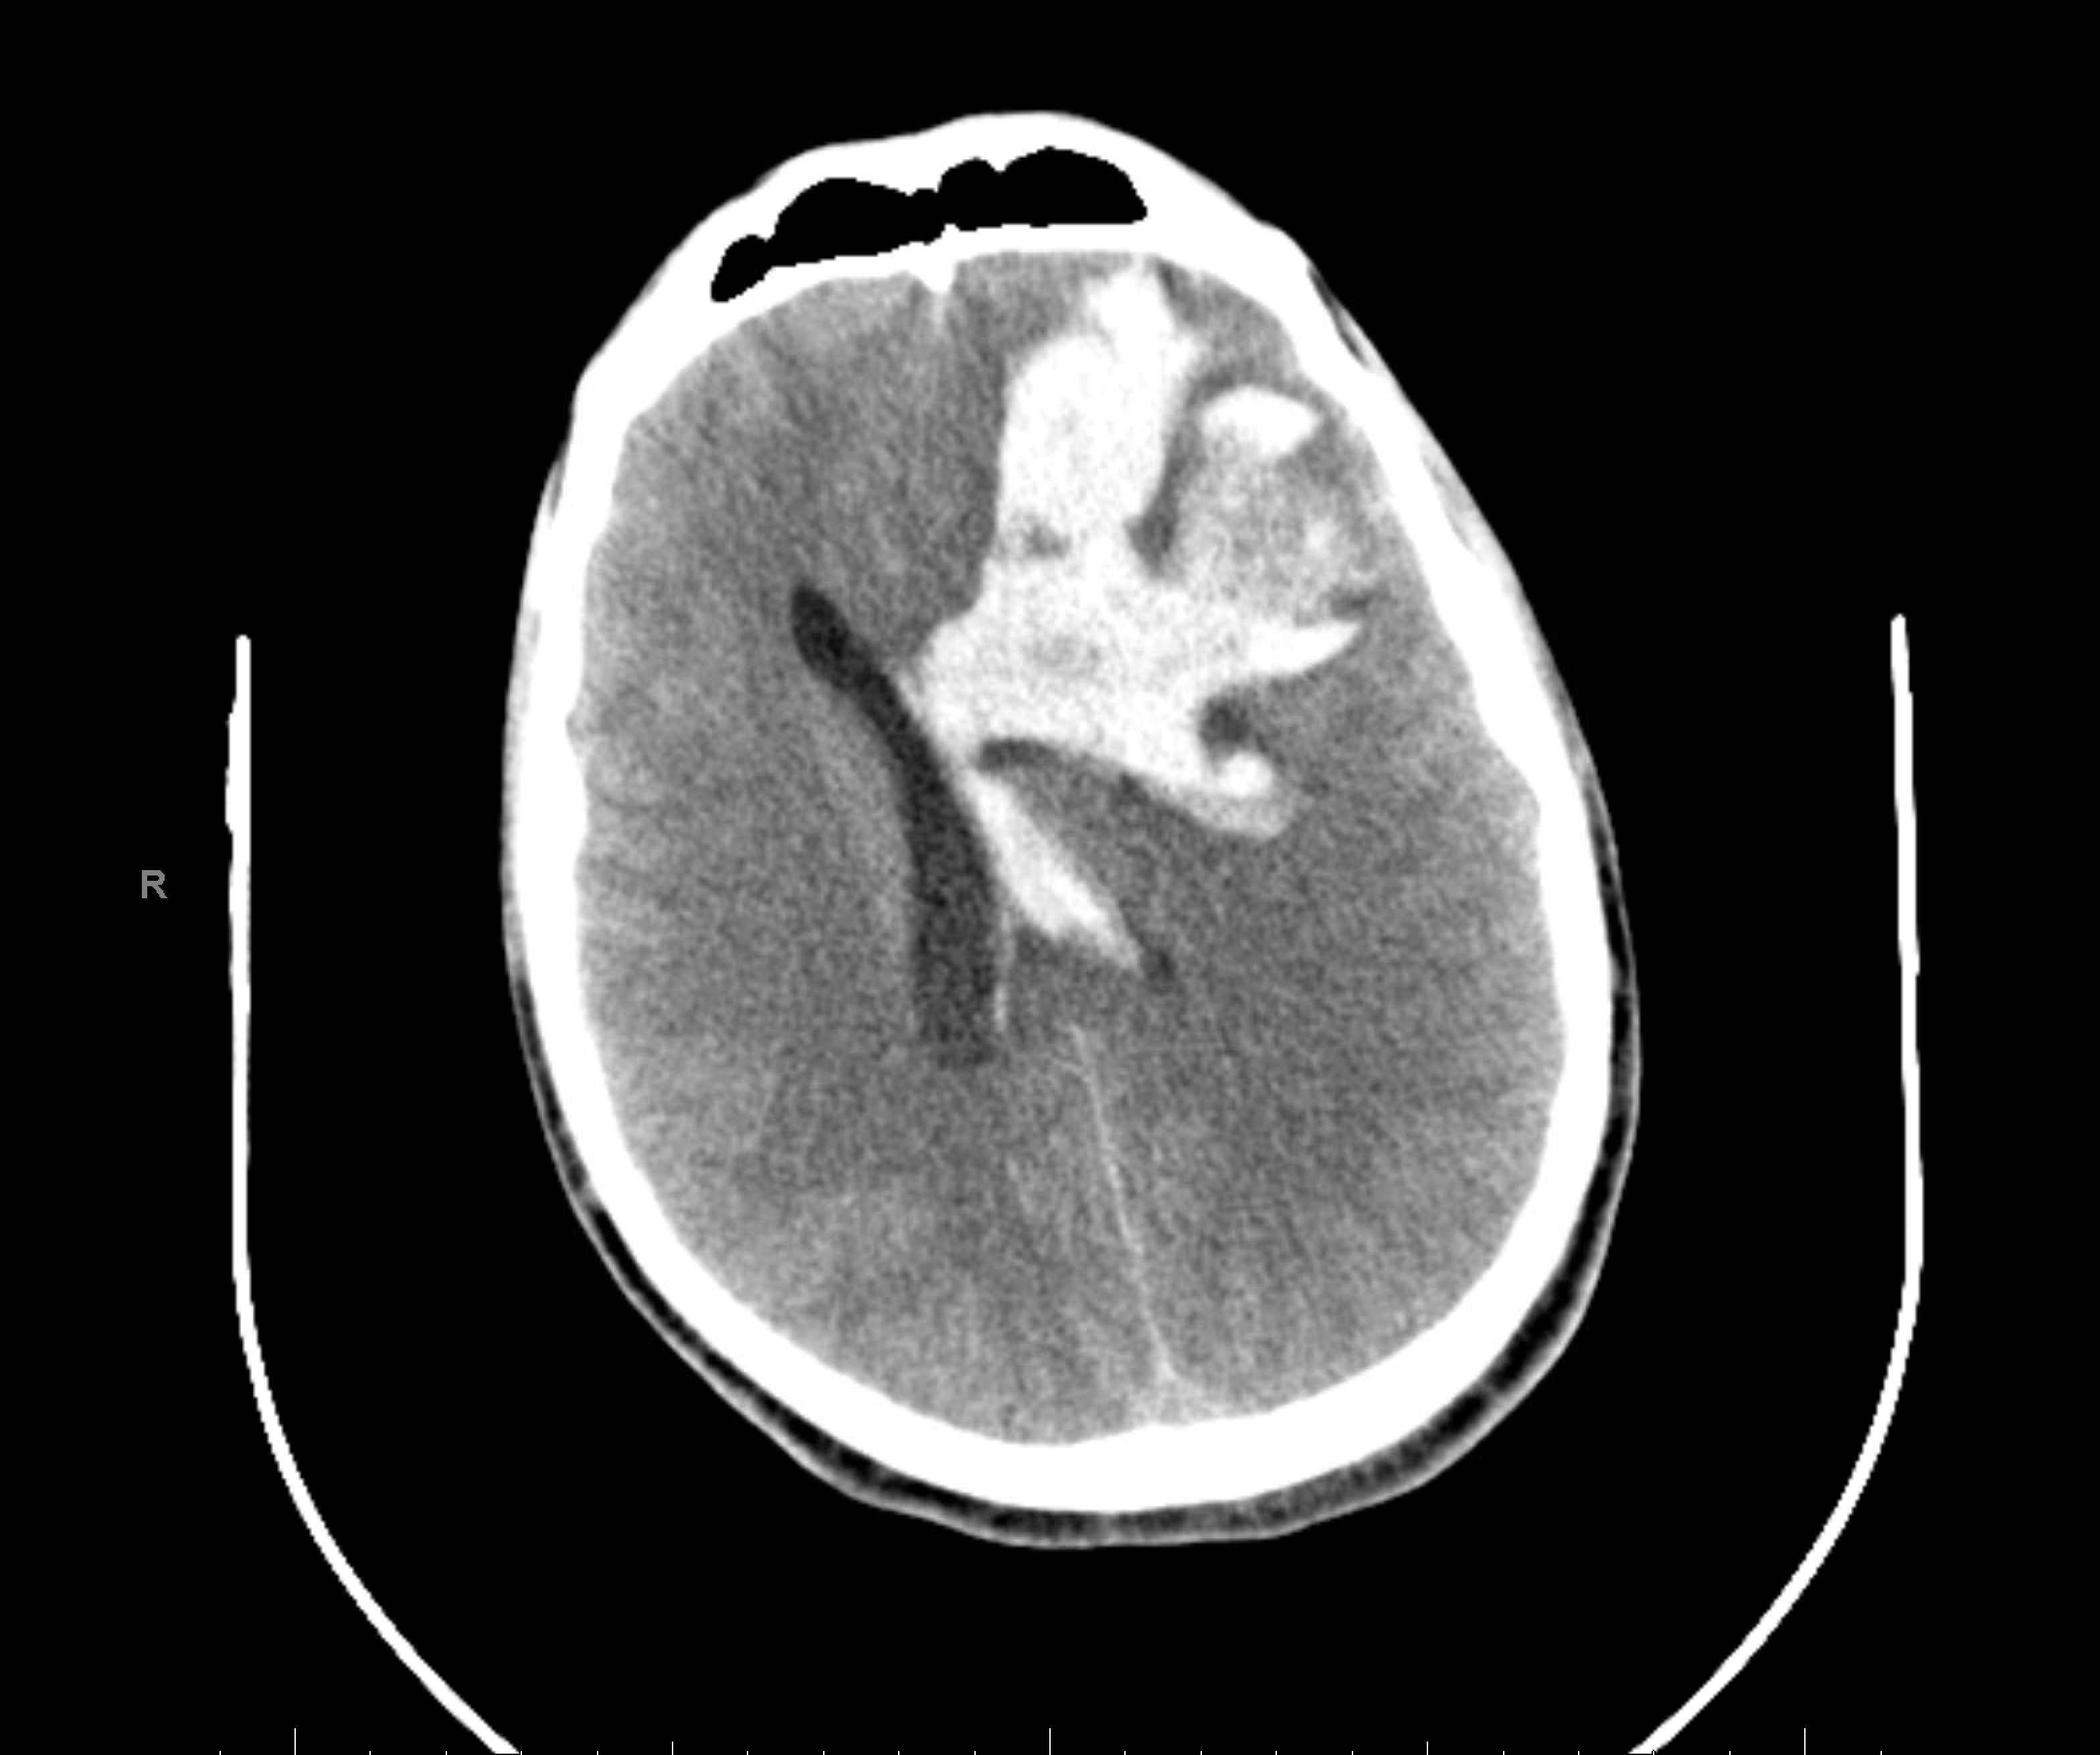

Age: 32

Sex: Male

Indication: Nontraumatic intracranial hemorrhage with cardiac arrest

Radiotracer: Tc99m ECD

Sample ReportAlthough no cerebral perfusion is present, there is an area of cerebellar perfusion, which is not consistent with brain death. This exam may be repeated in 24 hours if clinically indicated.